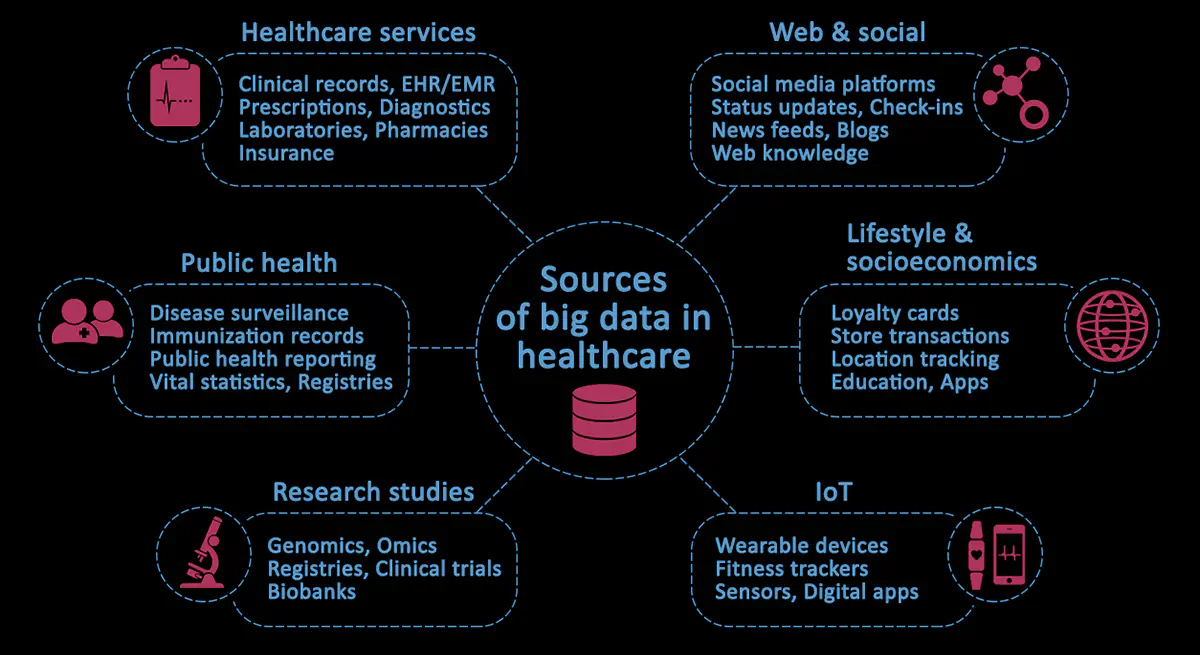

Big data in healthcare is multifaceted, noisy, and dynamic. Almost every interaction, such as a doctor ordering medicine on behalf of a patient, or a receptionist booking an appointment, or an insurance company receiving updates from patients and providers following the completion of treatment, generates data. Vast quantities of it.

Besides clinical notes, medical records and insurance claims, there are other less tangible sources of health-related information, such as data from wearable devices, fitness trackers and social media. Some of this data may be chaotic and unstructured. However, within this diversity lies a tremendous opportunity for deriving new clinical insights based on a much broader set of data.

This graph provides an overview of the major sources of big data in healthcare: